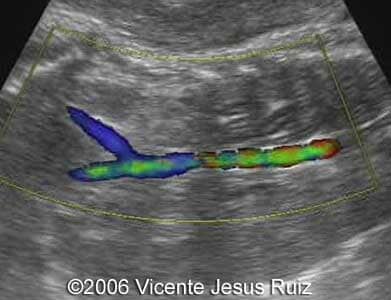

Absence of renal arteries

5